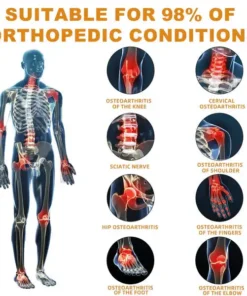

The ArthroFree™ Bee Venom Pain-Relief Bone Healing Cream is celebrated for its efficacy in addressing a wide array of orthopedic conditions. These include osteoarthritis, rheumatoid arthritis, bursitis, tendinitis, osteoporosis, gout, carpal tunnel syndrome, ligament sprains and strains, bunion deformities, and tennis elbow.